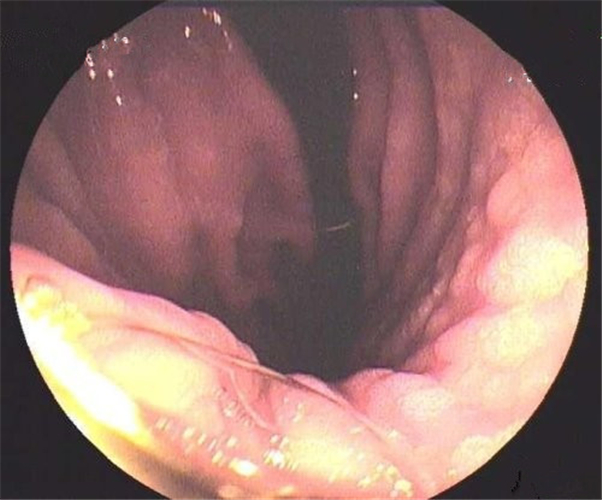

輕型淺錶慢性胃炎